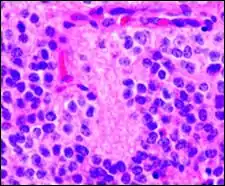

Homer Wright pseudorosette

A Homer Wright pseudorosette is a type of pseudorosette in which differentiated tumor cells surround the neuropil.[15] Examples of tumors containing these are neuroblastoma, medulloblastoma, pinealoblastoma, and primitive neuroectodermal tumors of bone. Homer Wright rosettes are considered "pseudo" in the sense that they are not true rosettes. True rosettes are Flexner–Wintersteiner rosette, which contain an empty lumen. Homer Wright rosettes contain abundant fibrillary material. They are named for James Homer Wright.

Structure of a Homer Wright pseudorosette